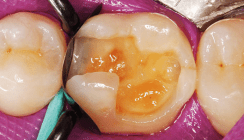

Die Bilder zeigen Merkmale, die bei dieser Methode wichtig sind:

• Kaum sichtbare Karies (Abb. 3a, 4a, 5a, 6a, 7a)

• Biofilmklumpen ohne/mit Blut (Abb. 3b, 4b, 6b, 7b)

• Entzündlich gerötete Pulpa (Abb. 3c, 4c, 6b, 7b)

• Weiße, obliterierte Pulpa (Abb. 5b).